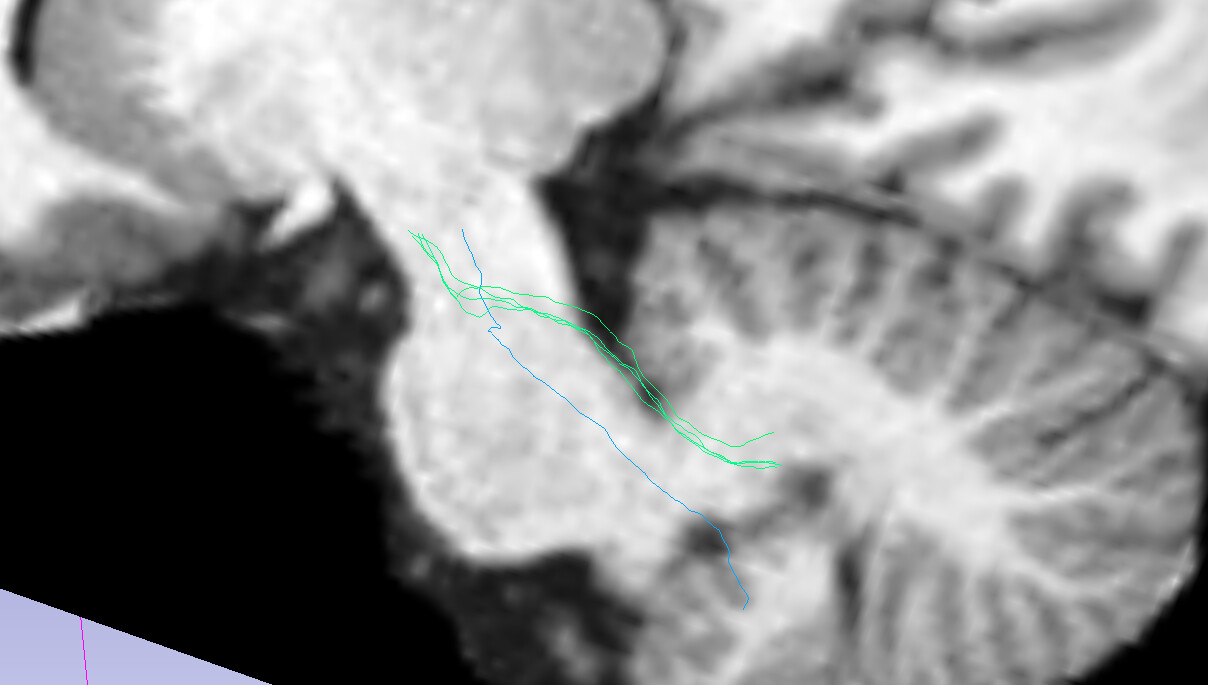

The below screenshot shows a subset (1%) of the 3.5 M streamlines:

Although it is a small fraction it shows the trend IMO.

The extracted MCP looks like this (the sagittal cut is at the midline):

So not quite right either, as streamlines climbs through the SCP and do not travel across the pons. My extraction should not be a problem since it is working OK on other tractography data.

SCP: